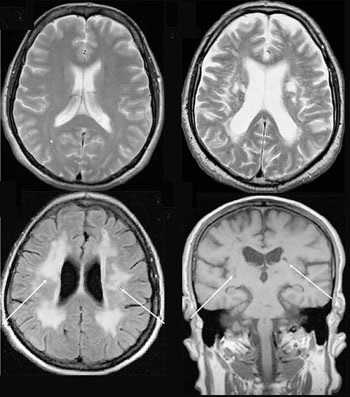

Что покажут снимки МРТ шеи у ребенка с лимфангиомой

- Заполненное жидкостью образование хорошо визуализируется на Т2-взвешенных изображениях

- Интенсивность сигнала на Т1-взвешенных изображениях зависит от содержания белка и наличия кровоизлияний

- Возможен уровень жидкости в пределах кисты (кровоизлияние)

- Отсутствие определяемого кровотока

- Умеренное контрастное усиление перегородок

- Имеется объемный эффект.

МРТ в режиме подавления сигнала от жидкости. Лимфангиома (стрелки) имеет гиперинтенсивный сигнал. Окологлоточный компонент опухоли смещает и сдавливает просвет глотки.